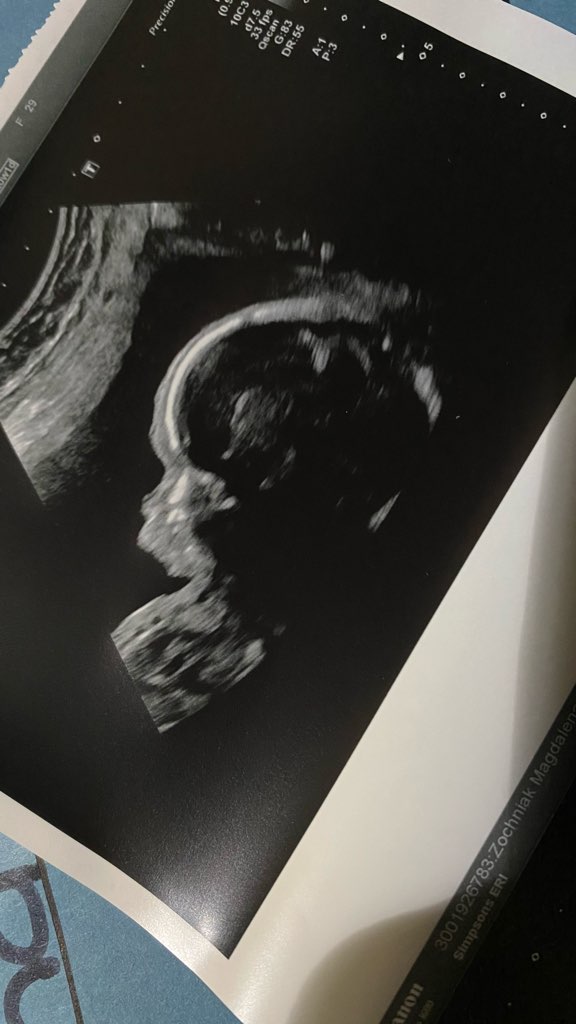

@Marta1991 super ze wszystko w porządku bardzo się cieszę ❤️ sama tez bym od razu jechała na szpital także bardzo się cieszę 😗😗 ja po badaniach trwało długo i wszystko w porządku wiadomo 100% nie daje ale cieszę się bardzo ze do tej pory wszystko jest ok wszystkie narządy pracują serduszko sprawne z czterema komorami główka tez w porządku mała się tak ruszała ze musiałam kilka razy wstawać z fotela podskakiwać 😁 No i dziewczynka 100%

• IMG_5495.jpg

IMG_5495.jpg

63,8 KB · Wyświetleń: 101